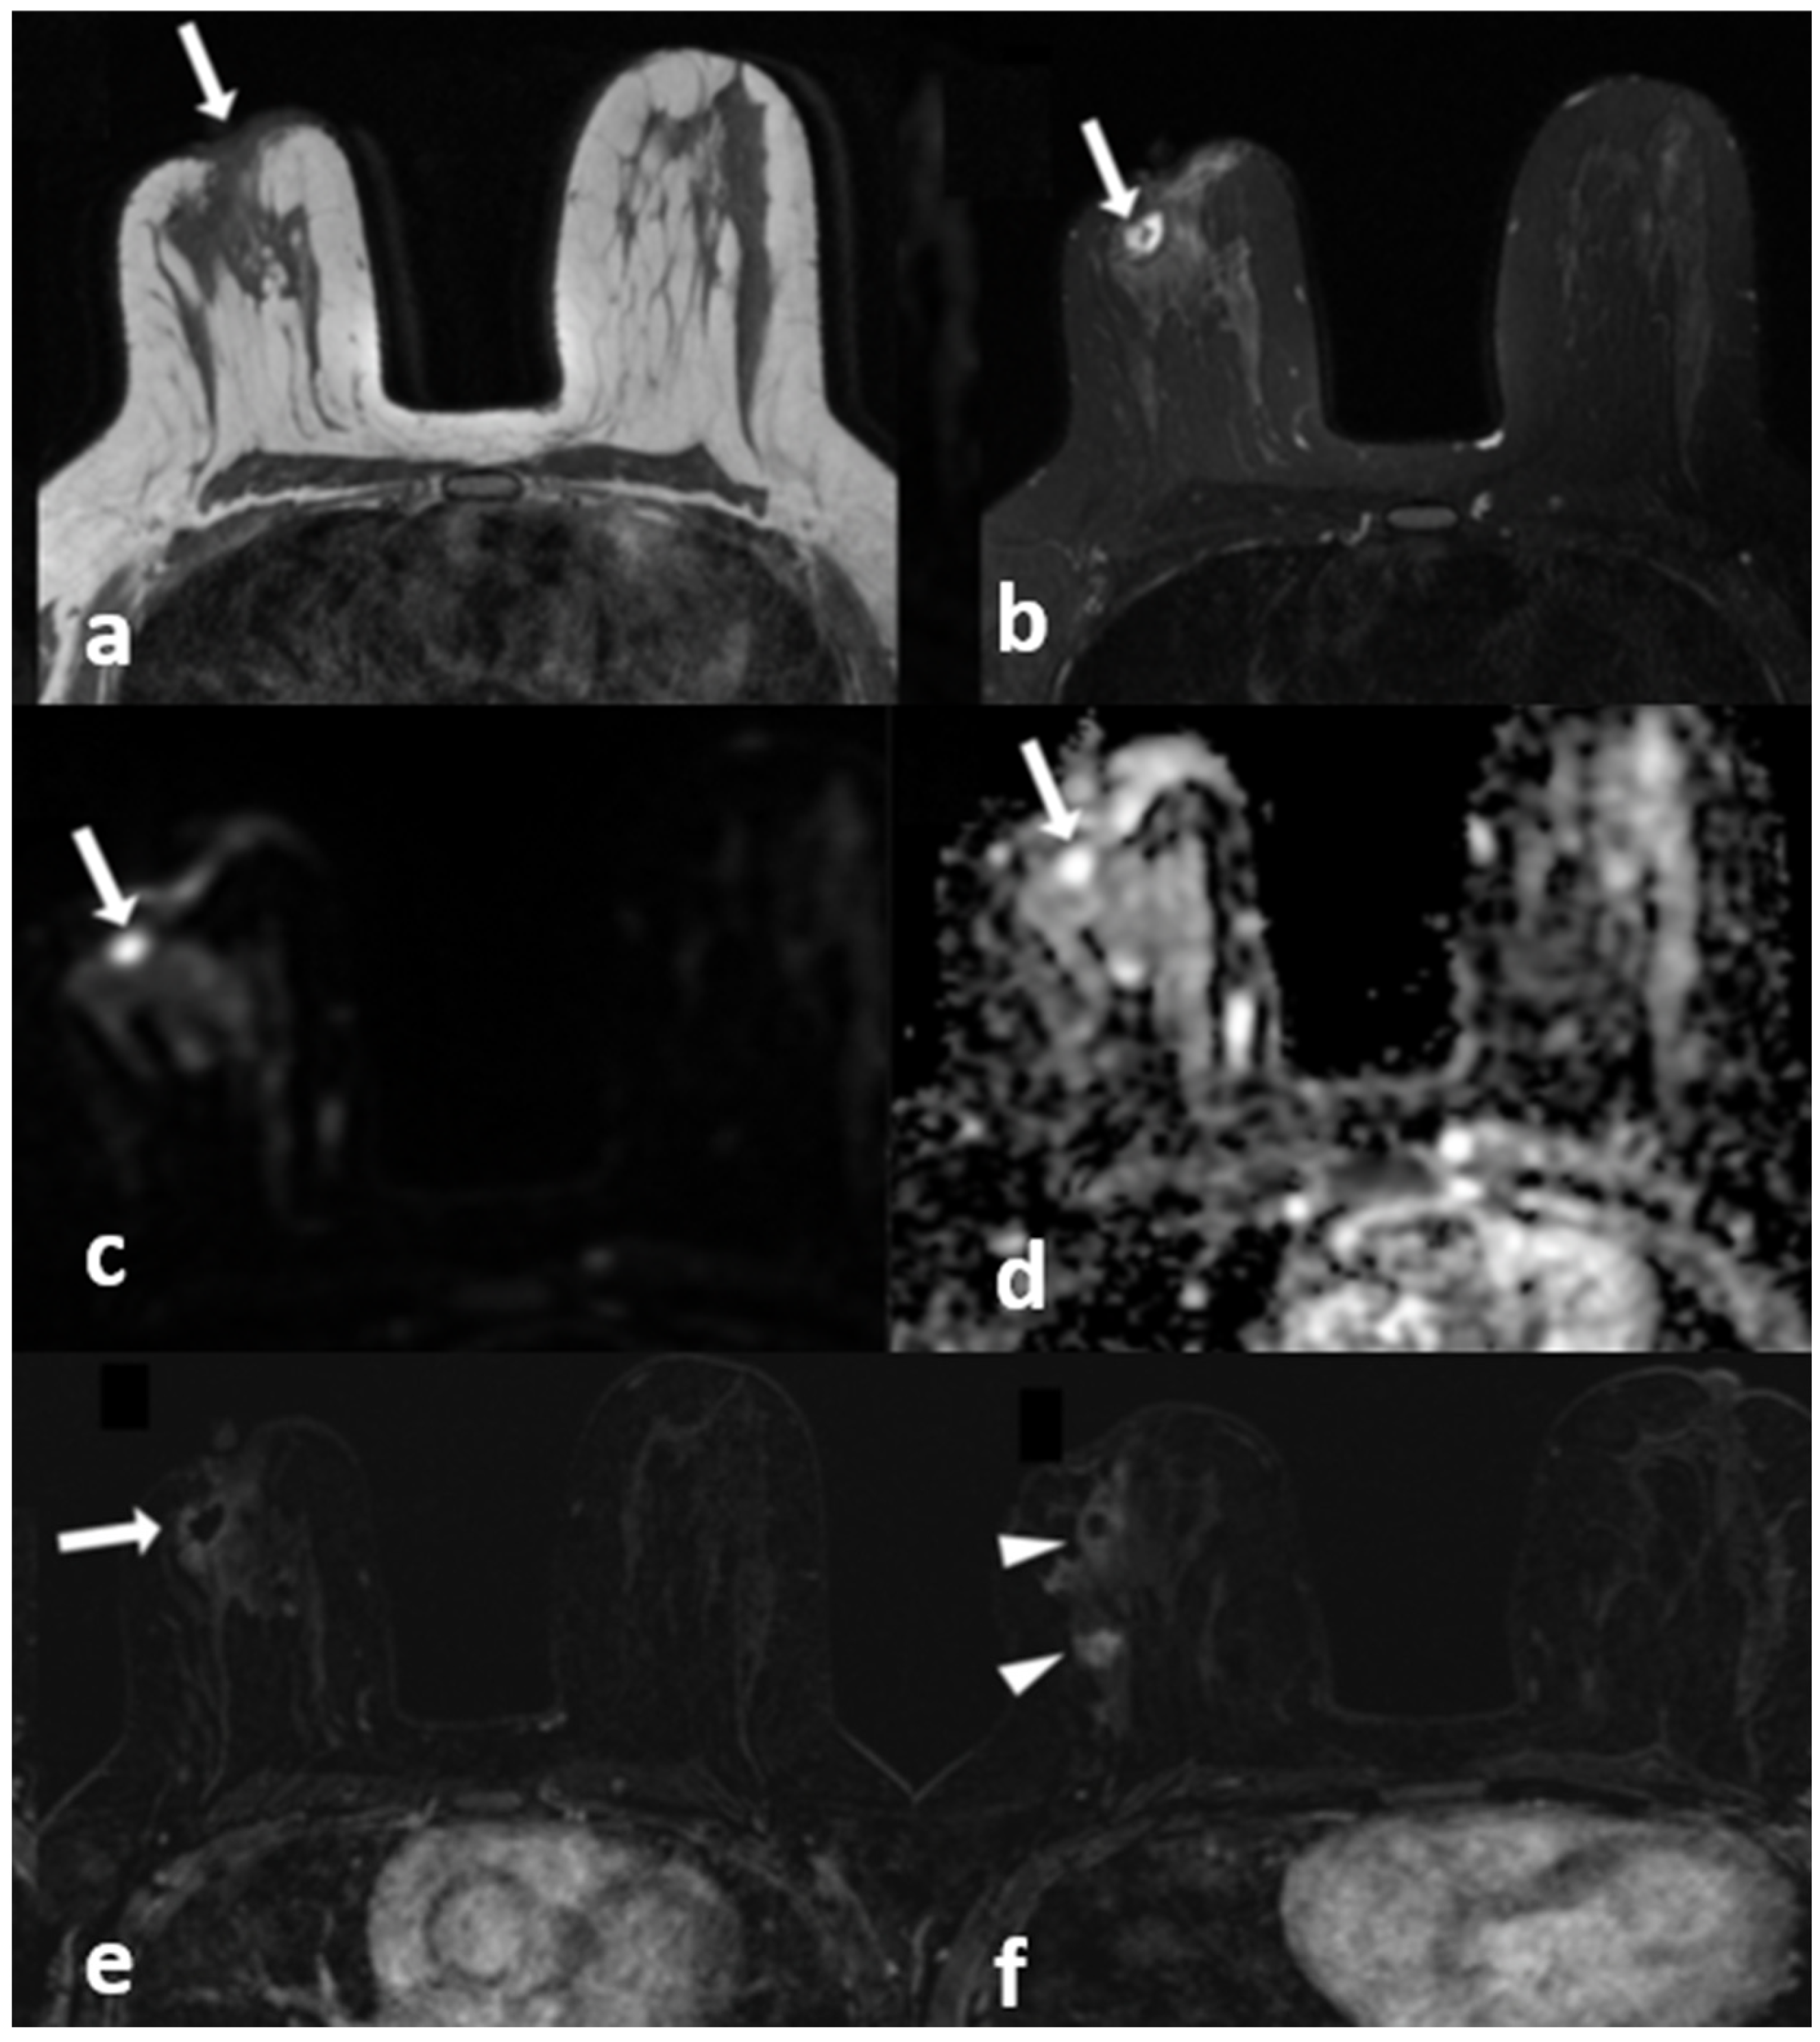

Cystic lesions with enhancing walls were more diagnostic for IGM in general (Table 5). Cysts with thin (p < 0.05) or thick walls (p = 0.001) as well as multiple cysts with enhancing walls (p < 0.001) were significantly more common in IGM (Figure 6). Multiple cystic lesions, cystic lesions draining to the skin and skin fistulas were detected more often in IGM with a significant difference (p < 0.001, p < 0.001 and p < 0.05 respectively). The number of cases with cysts with irregular walls did not show any difference.

Figure 6.

A 42-year-old woman with histopathologically proven invasive ductal carcinoma involving the right breast. (a) T1-weighted fast spin echo axial MR image of the patient shows parenchymal asymmetry in the retroareolar region along with nipple retraction (arrow). (b) Axial fat-saturated T2-weighted fast spin echo MR image, corresponding to (a), which reveals a cystic lesion (arrow) with a moderate signal increase in the parenchyma. (c) Diffusion-weighted and (d) ADC map show that the cystic lesion had no restriction of diffusion (arrows). (e) Contrast-enhanced subtracted image demonstrates a slight thin wall enhancement around the cystic lesion (arrow); (f) following the inferior image to (e) shows similar contiguous lesions demonstrating peripheral slight enhancement in the adjacent parenchyma (arrowheads).